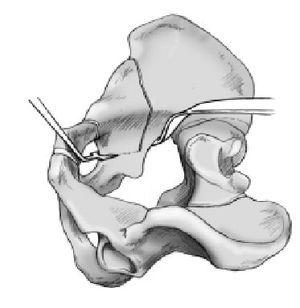

Figura 11 Primer paso de la segunda osteotomía. La segunda osteotomía se realiza en dos pasos. Es especialmente importante identificar la escotadura ciática mayor. Primero se introducirá un Hohmann romo desde dentro, luego otro desde fuera hacia la escotadura. Se deberían encontrar las dos puntas de los dos separadores. El separador introducido desde fuera debe asegurarse que vaya subperióstico (fig. 9), para evitar lesionar vasos o nervios. Se diseca la superficie medial del acetábulo (lámina cuadrilátera) con el periostiotomo de Cobb. Este gesto se prolonga hacia ventral hasta el agujero obturador, hacia dorsal hasta la escotadura ciática mayor, hacia proximal hasta la entrada de la pelvis y hacia distal hasta el hueso isquion. Se debería empujar un separador de Hohmann hasta el extremo distal de la espina ciática.

Figura 12 La parte supraacetabular de la osteotomía se inicia en el punto medio entre la espina ilíaca anterosuperior y la espina ilíaca anteroinferior y se localiza en cualquier plano perpendicular al paciente. Tendría que finalizar 1 cm antes del reborde óseo de la escotadura ciática mayor. El osteotomo apunta a la parte media de la columna posterior con la pierna flexionada. La sección se haría con una sierra oscilante y marcada previamente con electrocauterio. La osteotomía se realiza transversalmente al eje longitudinal del paciente en decúbito

y verticalmente respecto a la mesa operatoria.

Figura 13 Segundo paso de la segunda osteotomía. Tras terminar el primer corte con sierra se realiza el segundo corte con un escoplo apuntando a la espina ciática. Este osteotomo realiza

un ángulo de 110-120º respecto a la primera sección. Aquí se ha de ir con precaución en no ir demasiado dorsal, ya que puede romperse la columna posterior. De otro modo se tiene que ir bastante dorsal para evitar abrir la parte dorsal de la cadera. En este paso se utilizará un escoplo angulado 30º. La osteotomía se inicia al final de la osteotomía ilíaca y se dirige hacia el separador que se localiza tras la espina ciática. Cuando se sostenga el mango del escoplo absolutamente vertical, se localizará el filo en el plano correcto paralelo a la columna posterior. Esta osteotomía transcurre paralela y aproximadamente 1 cm por delante del límite posterior de la columna dorsal. Al acabar tiene una longitud de unos 4 cm. En todo momento el cirujano debe tener cuidado en mantener la misma distancia al límite posterior de la pelvis.